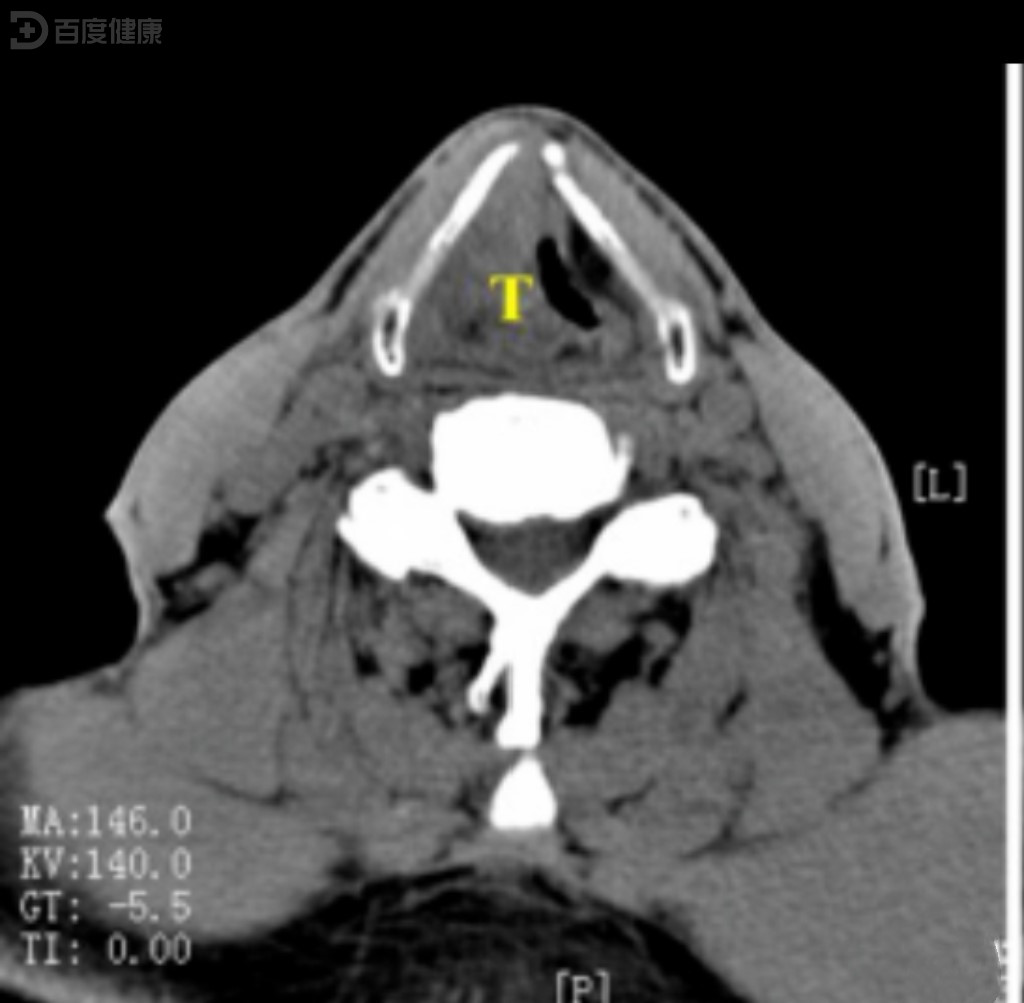

ct诊断:右喉癌(声门上型),伴右颈淋巴结转移.

喉癌的影像学诊断_声门